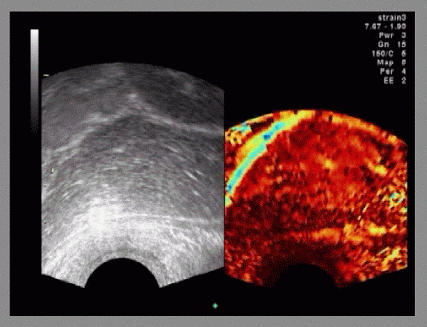

Echtzeit Elastographie: in vivo Mamma Karzinom (jpg)

Echtzeit Elastographie: in vivo Mamma Karzinom (10 MB)